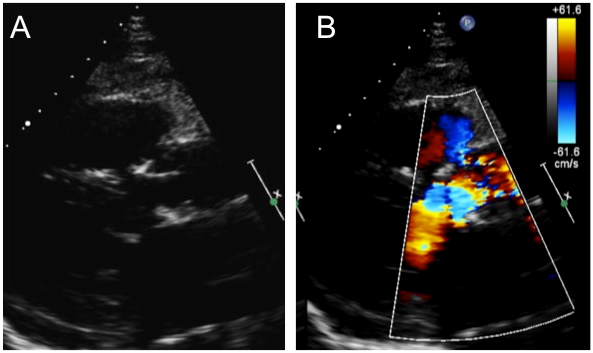

A 66-year old ex-smoker who presented with gradual deterioration with dyspnoea (NYHA II) that developed over 3-years. Past medical history included hypertension and hypercholesterolaemia. Examination was unremarkable apart from an ejection systolic murmur. A transthoracic echocardiogram confirmed a calcified aortic valve with severe aortic stenosis (EOA 0.7cm2, MG 53mmHg), mild aortic regurgitation (vena contracta 0.3cm) (Figure 1) and severe three-vessel disease involving the left main stem, the ostial and distal left anterior descending and mid circumflex and distal right coronary artery. His haematological investigations revealed only a minimally raised ESR (43mm/hour). His Logistical Euroscore II was 1.1%. He underwent an elective tissue aortic valve replacement using a 25mm Perimount Magna Ease bioprosthesis and coronary artery bypass grafting. This involved the left internal mammary artery grafted to the left anterior descending and a saphenous venous graft to the intermediate and right coronary artery. On sternotomy he was found to have a completely black aorta, aortic valve and heart (Figure 2). Histological analysis of aortic wall and leaflet tissue diagnosed alkaptonuria (Figure 3). Patient had a good post-operative recovery and on discharge was referred to clinical geneticists for further testing. He remains well on 2-year follow-up.

Figure 1 Parasternal long axis transthoracic echocardiogram (A) demonstrating thickened aortic valve leaflets with a stenotic valve on colour flow Doppler (B).